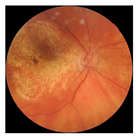

| No. | Fundus Image | Grad-CAM | Group | PRS | CNN | CNN+ML |

|---|---|---|---|---|---|---|

| 1 |  |  | Control | −2.13 | 0.63 | −0.34 |

| 2 |  |  | Control | −2.61 | 1.80 | −1.48 |

| 3 |  |  | AMD | 1.08 | 0.52 | −0.60 |

| 4 |  |  | AMD | −0.39 | −0.16 | −0.41 |